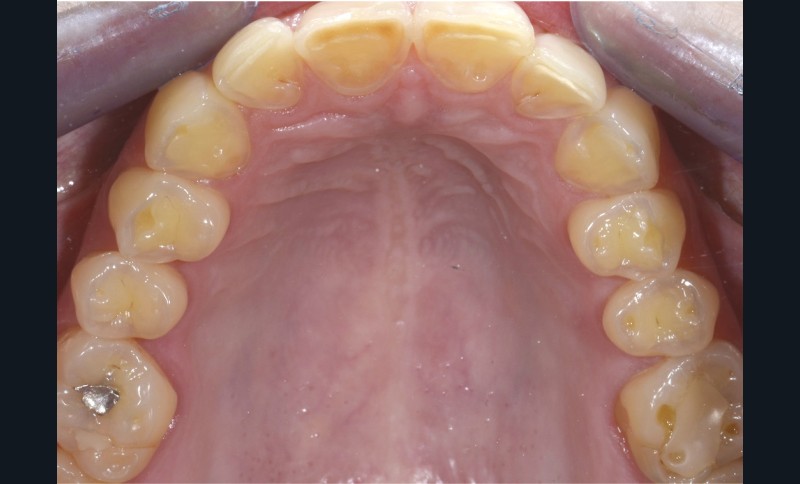

Une patiente âgée de 28 ans se présente en consultation avec une inquiétude au sujet de ses dents postérieures : elle a observé une usure avec un « jaunissement » des faces occlusales et se plaint de sensibilités répétées (fig. 1 à 3).

L’examen général met en évidence un bruxisme nocturne ainsi qu’une consommation peut-être excessive d’agrumes.